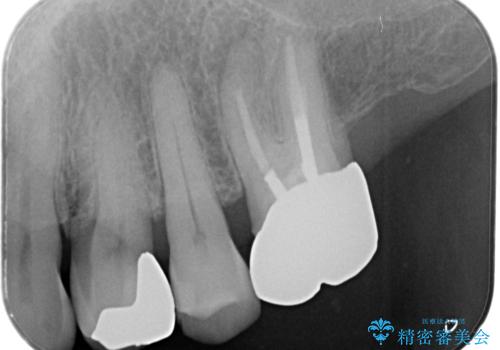

- 「フロスをしたら銀歯が取れた」を主訴に来院された患者様です。虫歯を除去した後、ゴールドインレーで治療を行いました。

隣の歯も虫歯になっており、その歯はCR(保険適応)で治療を行いました。

左上4はゴールドインレー、左上5はCR(保険適応)で治療を行いました。